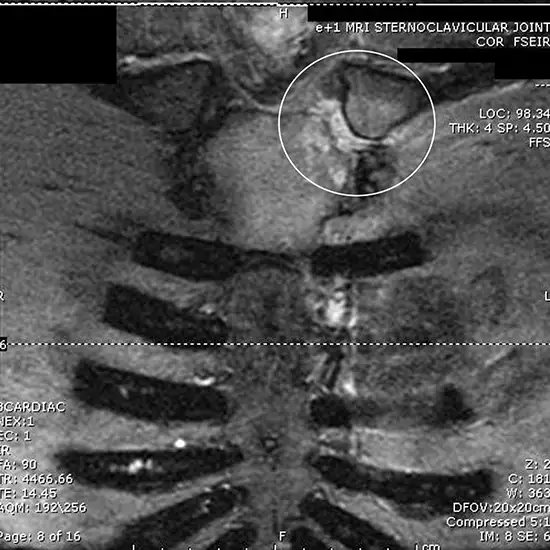

Magnetic resonance imaging (MRI) sternoclavicular joint examination is a non-ionizing technique that produces images of the joint located between the sternum and the clavicle.

MRI (Magnetic Resonance Imaging) screening arm is a non-invasive medical diagnostic tool used to obtain detailed images of the sternoclavicular joint located between the sternum and the clavicle. MRI Sternoclavicular Joint is used to show abnormalities in the sternoclavicular joint like fracture, injury, displacement, dislocation, tumors etc.